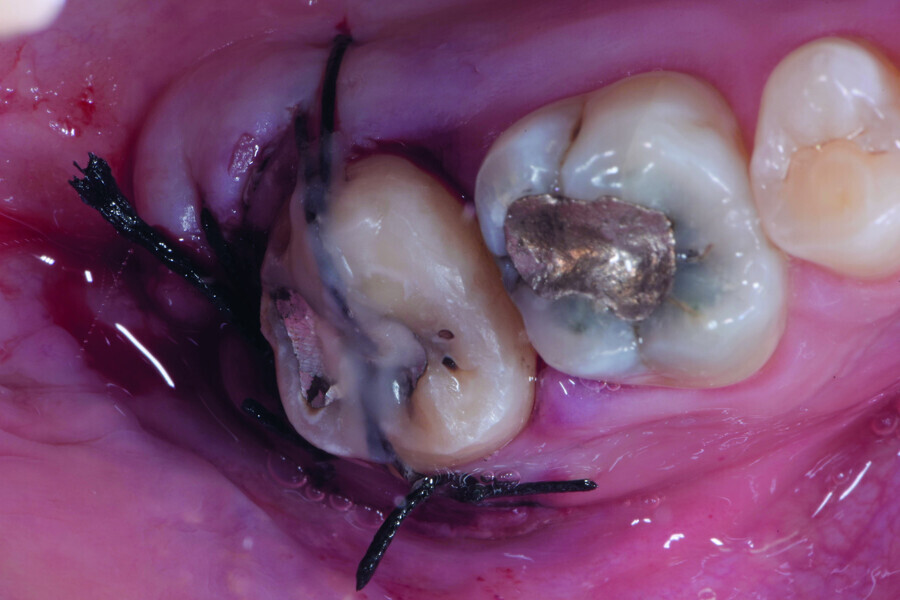

Fig. 12: Pulp chamber floor perforation, immediately after extraction.

Fig. 13: Pulp chamber floor perforation, tooth cleaned.